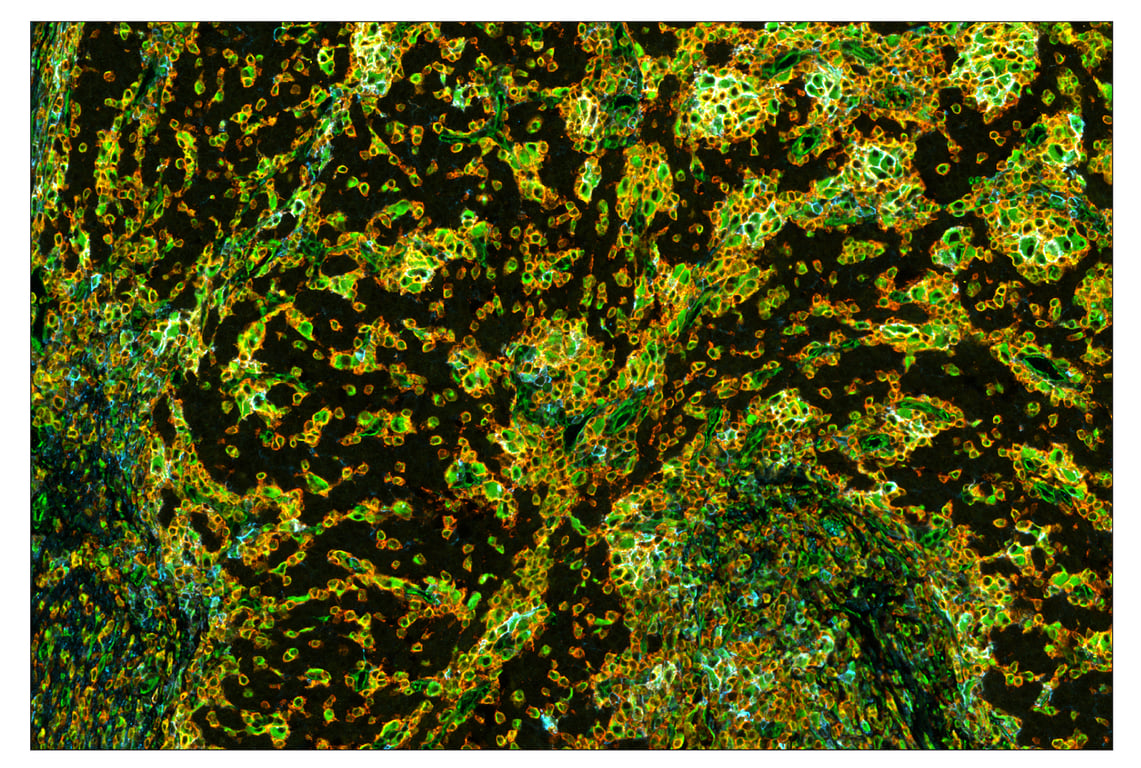

CD44 (E7K2Y) & CO-0030-488 SignalStar Oligo-Antibody Pair #51316

SignalStar multiplex immunohistochemistry (IHC) is an advanced technology for labeling multiple proteins simultaneously in tissue samples using specific primary antibodies and fluorescent detection reagents. This technology offers accuracy and reliability in visualizing and analyzing protein expression while maintaining spatial context and tissue architecture.

CD44 (E7K2Y) Rabbit Monoclonal Antibody (SignalStar™ Conjugate 0030) recognizes endogenous levels of total CD44 protein.